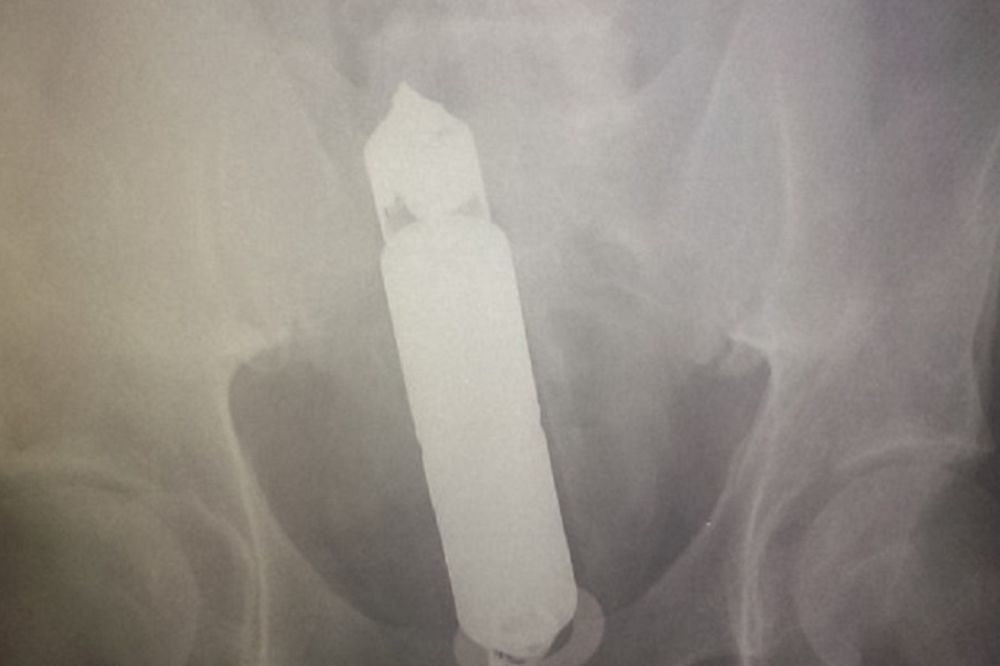

Bolnica u Dabllinu primila je penzionera (68) kako bi ga hitno operisala, a nas snimku su videli da je u njegovom stomaku dildo od 23 santimetra. TOTALNO UVRNUTO: 22 predmeta koje su ljudi uspeli da izgube u svojim zadnjicama! (FOTO) On je primljen sa bolovima u stomaku i leđima, a nakon rendgena podvrgnut je hirurškoj intervenciji. Nije poznato kako je do ove nesreće došlo, ali je dildo uspešno odstranjen. (Espreso.co.rs / Izvor: DailyStar Foto: Ilustracija)